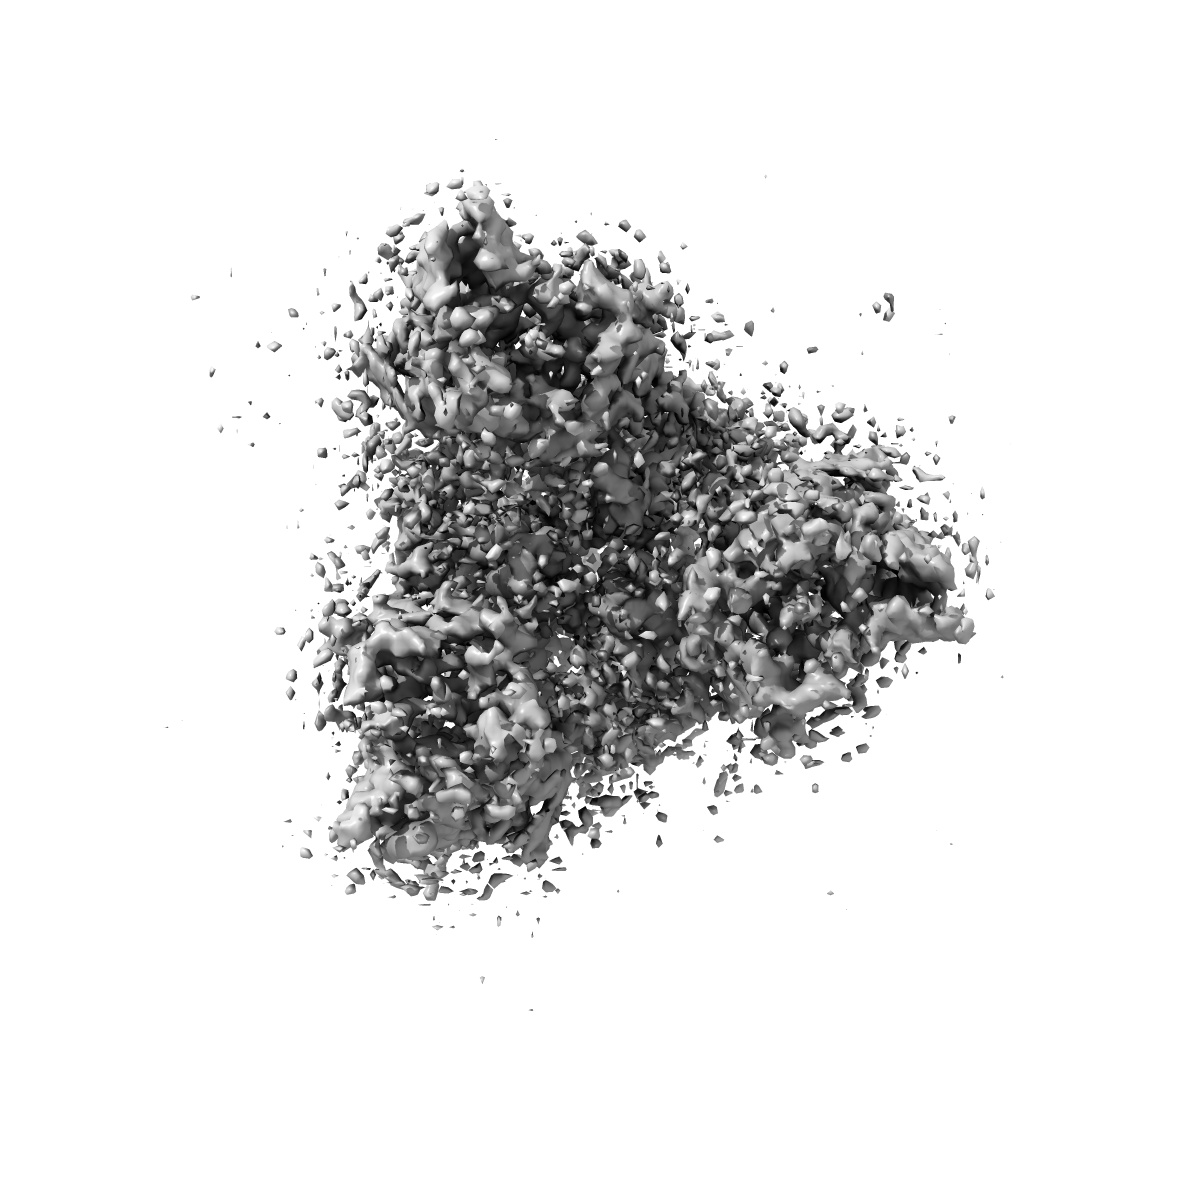

Major cryo-EM structure of S protein trimer of SARS-CoV2 with K-874, composite map

Single-particle3.9 Å